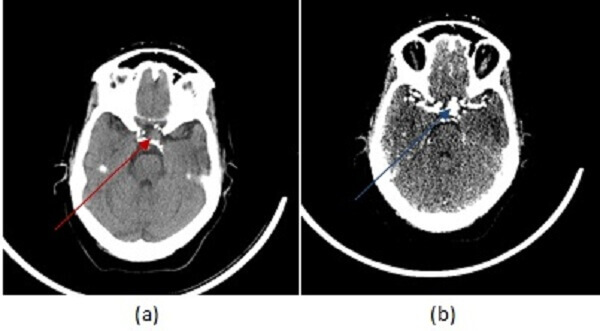

Figure 1: (a, red arrow) non contrast head CT demonstrates a rim calcified mass in the left cavernous sinus projecting towards the suprasellar space. (b, blue arrow) Axial image from a CT angiogram shows vascular enhancement of this mass . These findings are consistent with an aneurysm, likely fusiform. (c) Coronal minimum intensity projection from the CTA shows fusiform dilation of the left cavernous carotid.